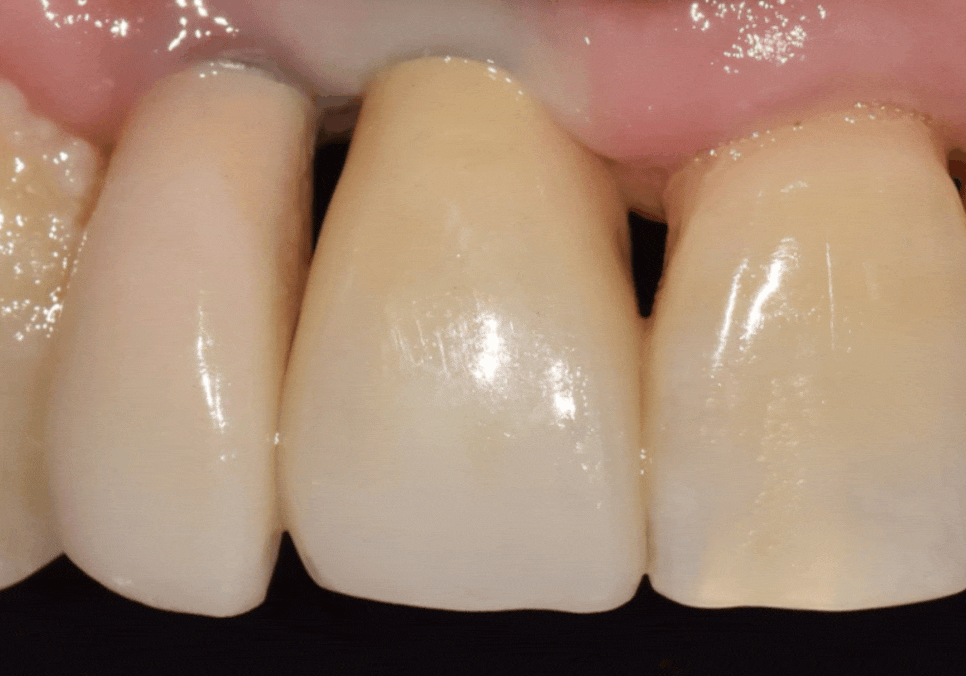

그래서 저희는 중앙 앞니

끝부분의 길이를 미세하게 늘려보기로 했어요.

1mm 정도의 아주 작은 변화였지만,

이 미묘한 차이가 환자분이

느끼는 만족감에는 큰 영향을 준답니다.

중앙 앞니 길이를 인접한 치아와

조화롭게 맞춰준 다음,

오른쪽 앞니(#12)의 각진 부분도

조금 더 부드럽게 다듬어서

전체적인 배열을 완성했어요.